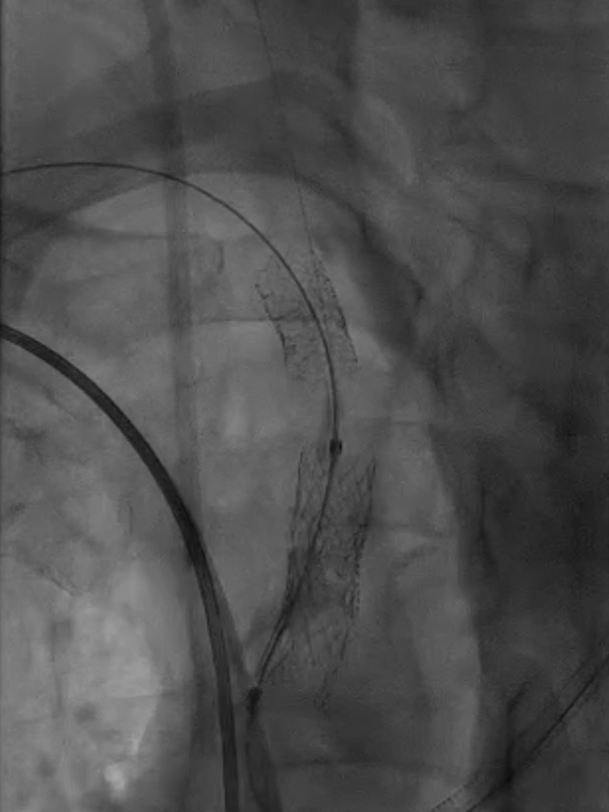

球囊扩张:采用同轴双导丝技术,以4×40mm、6×40mm球囊逐级扩张狭窄段;造影发现残存狭窄后,再次用6×40mm球囊扩张。

4*40mm球囊扩张

无名动脉支架

多角度造影

仍有残存狭窄

6*40mm球囊扩张

再次6*40mm球囊扩张

支架置入:通过“球囊带鞘”技术跟进长鞘至支架远端,采用同轴双导丝技术送入VBX8×29mm球扩覆膜支架,多角度造影定位后释放。

撤球囊时更进长鞘

至支架远端

同轴双导丝技术送入

VBX 8*29mm球扩覆膜

支架反复造影定位

释放支架